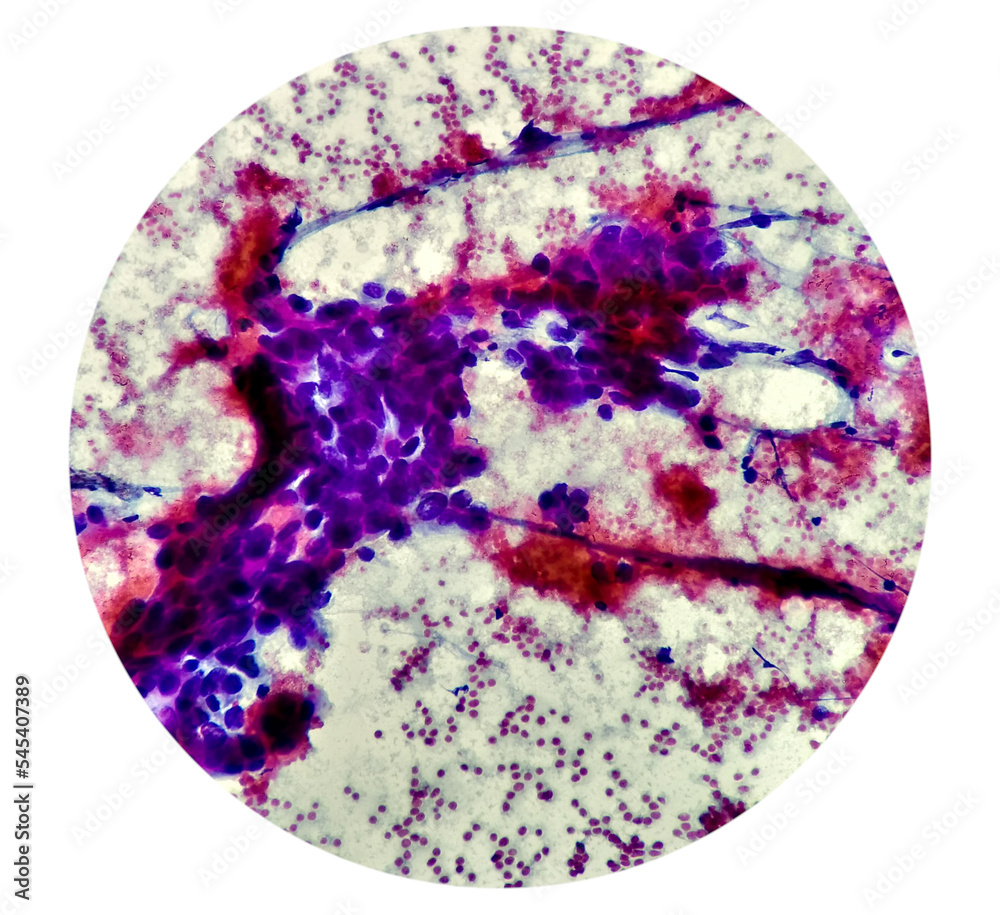

From stock.adobe.com

Intra abdominal mass(Cytology) Spindle cell positive Spindle Cell Sarcoma Abdomen A spindle cell sarcoma is a soft tissue tumor that originates in a bone. Initially a gastrointestinal stromal tumour (gist) was diagnosed, but his. Spindle cell sarcoma is a rare form of bone cancer or soft tissue cancer. An important group of such lesions are the gastrointestinal stromal tumours. An important group of such lesions. Spindle cell sarcoma is a. Spindle Cell Sarcoma Abdomen.

Cytological study of intra abdominal mass, Spindle cell Spindle Cell Sarcoma Abdomen Sarcomas are clumps of abnormal cells (tumors) that. Spindle cell sarcoma is a type of undifferentiated sarcoma. It can occur anywhere throughout the body, but it most commonly. Initially a gastrointestinal stromal tumour (gist) was diagnosed, but his. An important group of such lesions. Interpretation of gastrointestinal tract mesenchymal lesions is simplified merely by knowing in which anatomic layer they. Spindle Cell Sarcoma Abdomen.

Cytological study of intra abdominal mass, Spindle cell Spindle Cell Sarcoma Abdomen Initially a gastrointestinal stromal tumour (gist) was diagnosed, but his. An important group of such lesions are the gastrointestinal stromal tumours. An important group of such lesions. Spindle cell sarcoma is a rare form of bone cancer or soft tissue cancer. Interpretation of gastrointestinal tract mesenchymal lesions is simplified merely by knowing in which anatomic layer they are. Spindle cell. Spindle Cell Sarcoma Abdomen.